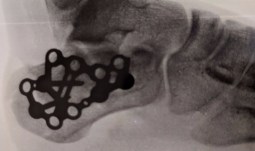

The multiple heel bone fractures of my son created such a trauma that forced us to set

aside the loss of my mother. I had to deal with the heart wrenching moments of helplessness. My husband and I faced the busy reality of doctor visits, surgery, extra day care routines, extra nutrition and his rehabilitation. My son had to deal with school, the injury and the college application. It has tested our stress tolerance level to the max. Our health is being tested, and it is a relief that we stay healthy to deal with the hardship.